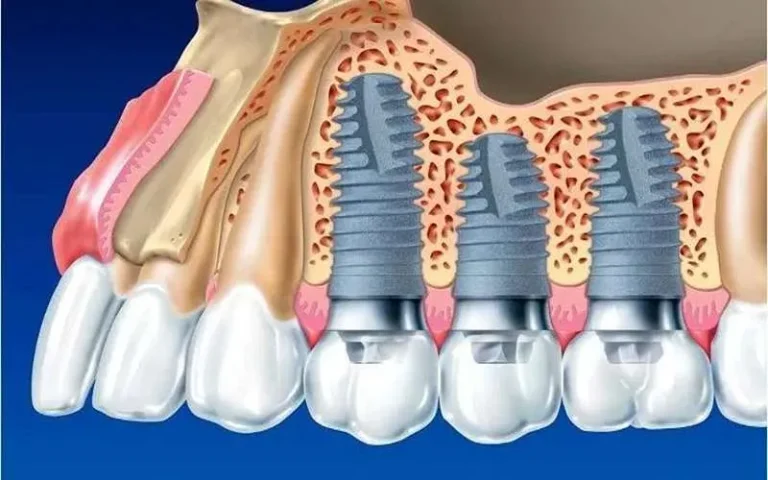

سینوس لیفت نوعی روش جراحی برای قرار دادن آسان تر ایمپلنت های دندان در دهان است. عده ای از افراد به کاشت ایمپلنت احتیاج دارند، اما حمایت استخوانی لازم برای کاشت دندان را ندارند.

در این مواقع عمل سینوس لیفت باز می تواند روشی موثر و کاربردی باشد. جراح با اضافه کردن استخوان به فضای بین دندان مولر و آسیاب می تواند تراکم استخوان فک بالا را بیشتر کند.

امروز دندانپزشکان به صورت گسترده از روش سینوس لیفت باز استفاده می کنند. به منظور انجام جراحی سینوس لیفت باز به استخوان با اندازه 5 سانتی متر احتیاج دارید. در روش سینوس لیفت باز، برش روی باف لثه ایجاد شده و بعد سینوس به بالا حرکت داده می شود.

پس از طی کردن این مرحله، قسمت خالی از طریق مواد پیوندی و پودر استخوان کامل و پر می شود. جراح باید به منظور انجام عمل سینوس لیفت باز تبحر زیادی داشته باشد. پس جهت انجام این عمل جراحی به هر مرکز دندانپزشکی مراجعه نکنید.